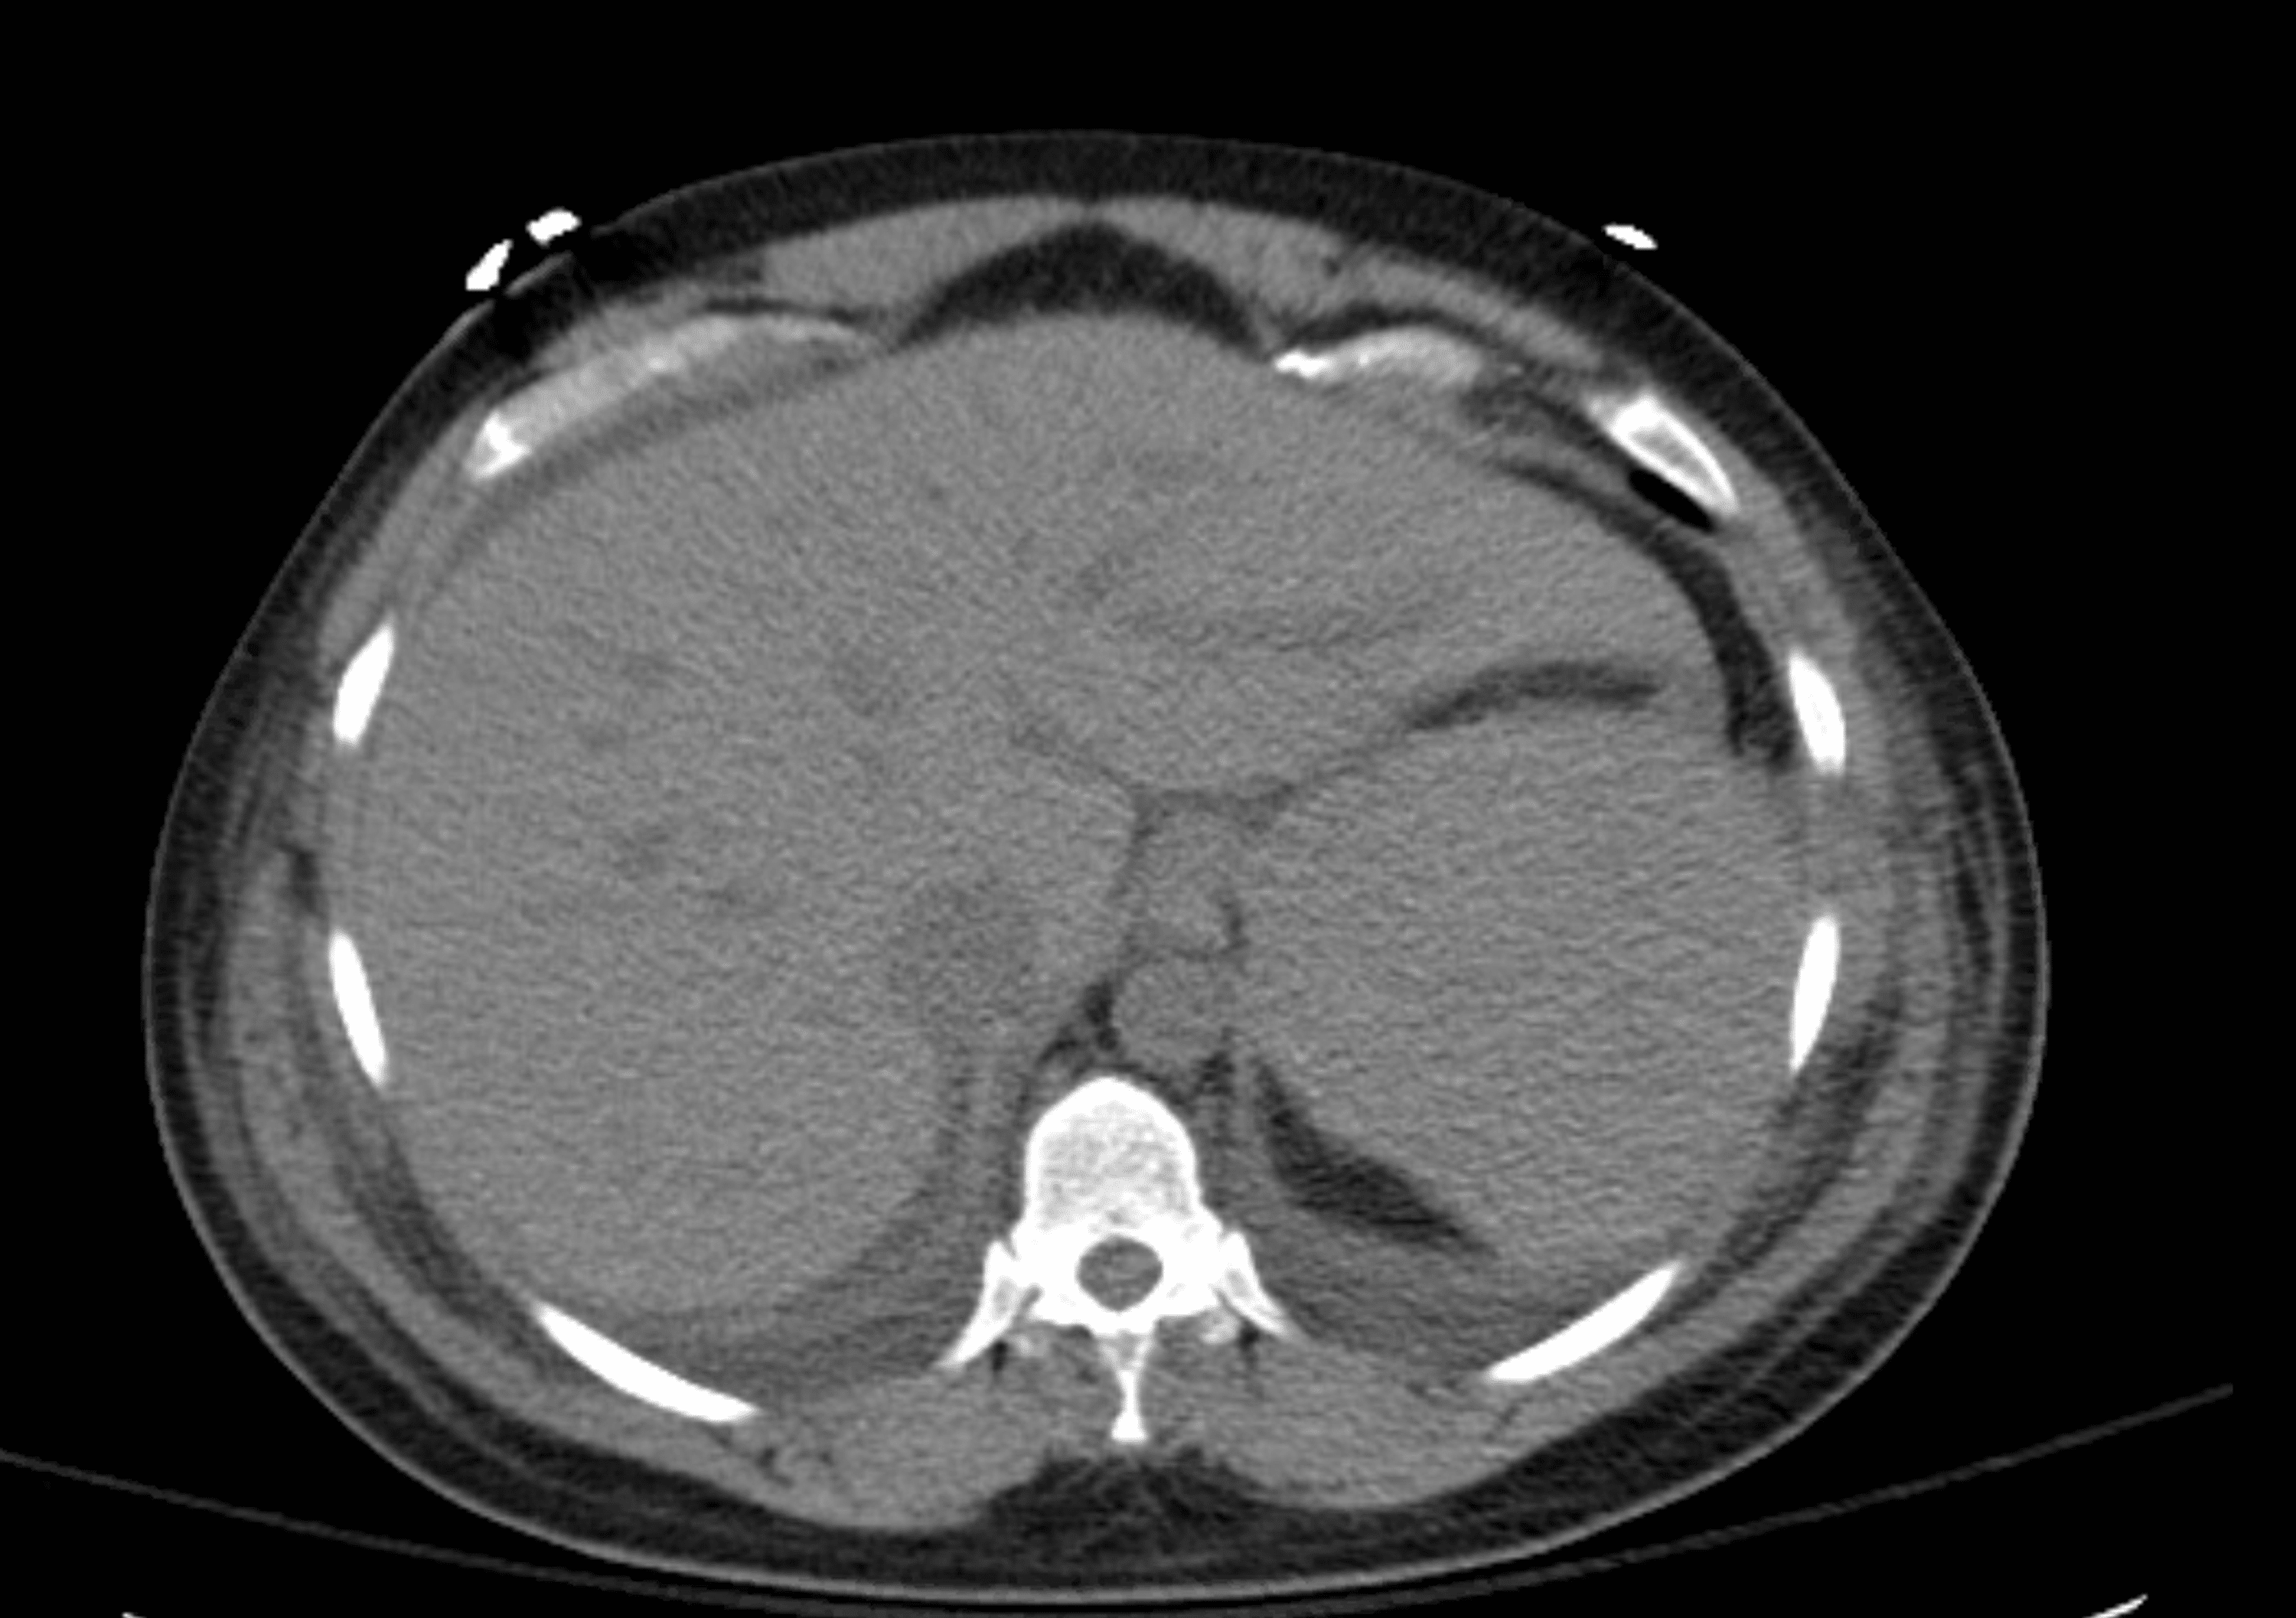

Figure 1 from Subcapsular Liver Hematoma A Rare Complication of Liver Enzymes High And Platelets Low It can be caused by many factors, including an enlarged spleen and decreased platelet production. Review any previous results to look for similar lower counts or a falling trend in. Decreased production, splenic sequestration and increased destruction. Thrombocytosis is the term given to the presence of an elevated platelet count and is most commonly defined as a platelet count of.. Liver Enzymes High And Platelets Low.